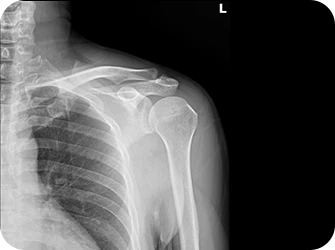

엑스레이 검사